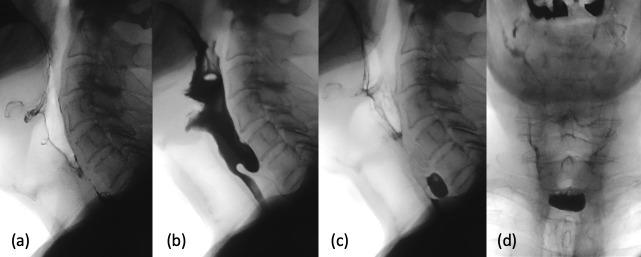

咽病理学的影像学表现。

Imaging of pharyngeal pathology.

The pharynx plays a significant role in swallowing and speech, and this is reflected in both its complex anatomy and degree of physiological motility. Patients who present with pharynx-related symptoms such as sore throat, globus, dysphagia or dysphonia will usually undergo visual and nasal endoscopic examination in the first instance. Imaging is frequently required to supplement clinical assessment and this typically involves MRI and CT. However, fluoroscopy, ultrasound and radionuclide imaging are valuable in certain clinical situations. The aforementioned complexity of the pharynx and the myriad of pathologies which may arise within it often make radiological evaluation challenging. In this pictorial review, we aim to provide a brief overview of cross-sectional pharyngeal anatomy and present the radiological features of a variety of pharyngeal pathologies, both benign and malignant.

咽在吞咽和言语中起着重要作用,这反映在其复杂的解剖结构和生理运动程度上。出现咽痛、咽部异物感、吞咽困难或发音困难等咽部相关症状的患者通常首先进行视诊和鼻内镜检查。影像学检查常需要补充临床评估,通常包括 MRI 和 CT。然而,透视、超声和放射性核素成像在某些临床情况下具有重要价值。上述咽的复杂性和可能发生的多种病理改变常常使影像学评估具有挑战性。在本影像学综述中,我们旨在简要概述咽的横断解剖结构,并介绍各种良性和恶性咽病变的影像学特征。